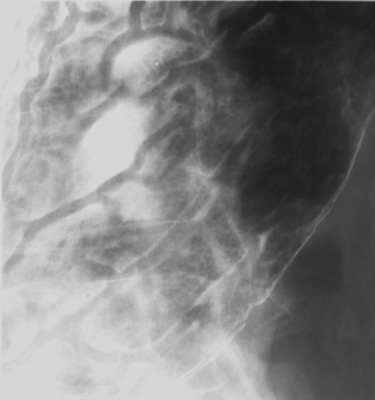

- Fundus (patient right lateral)